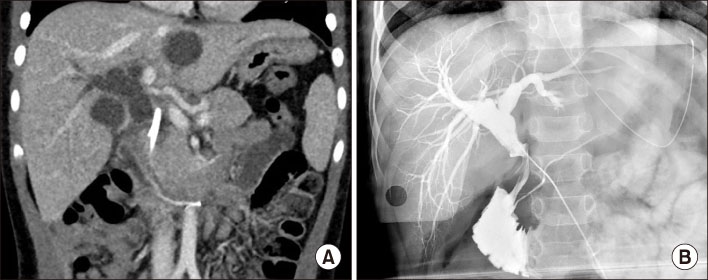

Fig. 4

Fig. 4 (A) CT scan taken at the 2nd admission shows the distal migration of endoscopic retrograde biliary drainage catheter with aggravated proximal biliary dilatation above the stricture site of mid-common bile duct. (B) Cholangiography during the operation.